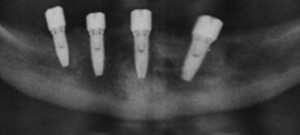

By tilting the two posterior implants, longer implants can be used in minimum bone volume, increasing bone-to-implant contact and reducing the need for vertical bone augmentation. The tilted posterior implants can be anchored in better quality anterior bone, reducing cantilevers and thus improving support of the prosthesis.

Good clinical results

Biomechanical measurements show that tilted implants, when part of prosthetic support, do not have a negative effect on the load distribution. The tilting of implants has been used in clinical practice for over a decade and has shown good results.